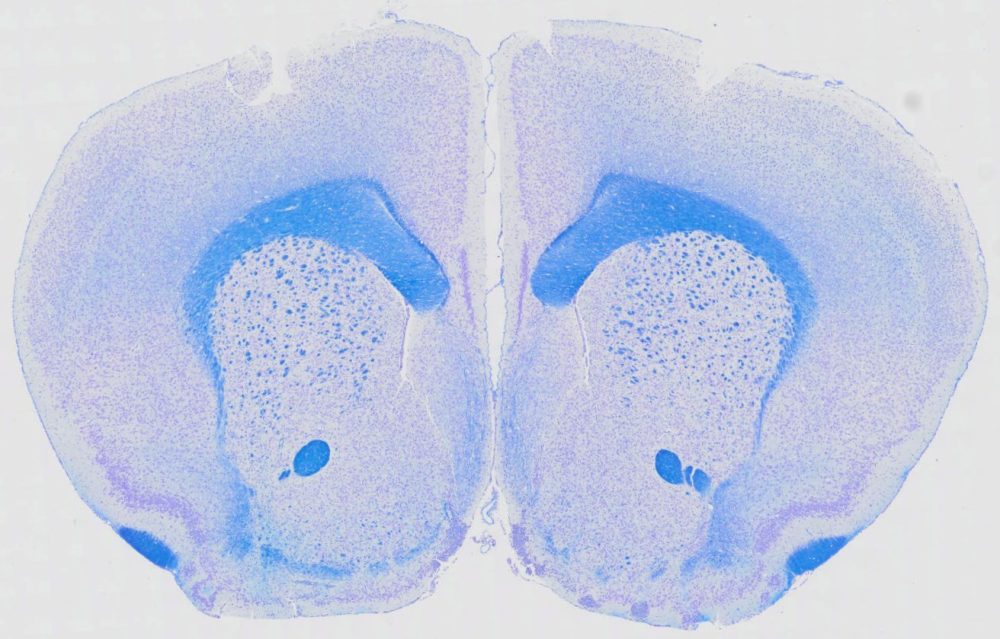

Luxol Fast Blue Stain Kit is designed for staining myelin/myelinated axons on formalin-fixed, paraffin-embedded brain and spinal cord tissue sections, as well as frozen sections. The myelin, including phospholipids, will be stained blue to green, and the neurons will be stained violet.This stain is commonly used for identifying the basic neuronal structure in brain or spinal cord tissue.

Results

- Myelin, including phospholipids —————-blue to green

- Neuron —————————————————-pink to violet

Positive Controls: Brain, spinal cord.